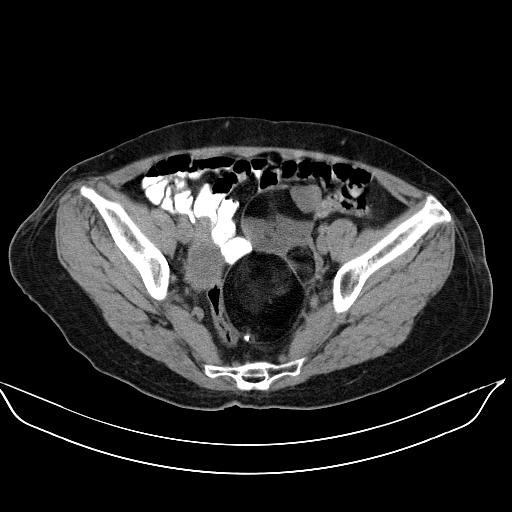

标题: CT17892:盆腔肿块

患者,女,61岁,无自觉症状,体检时发现盆腔肿块。

多发性畸胎瘤!

盆腔内多发性畸胎瘤。

典型畸胎瘤(皮样囊肿)